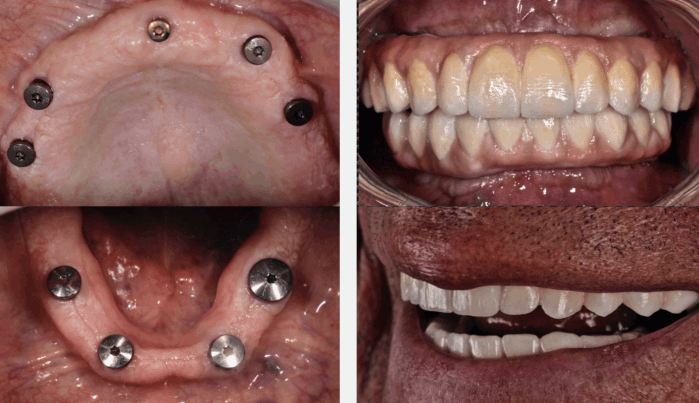

Descubre los increíbles resultados de nuestros tratamientos con esta galería de imágenes antes y después. En Bio Dental Clinic, combinamos experiencia, tecnología y atención personalizada para devolver la función, estética y confianza a cada sonrisa.